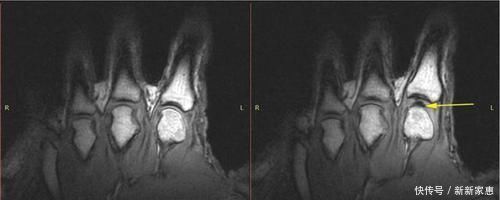

但在 2015 年,加拿大和新西兰的联合团队在 PLOS One 上发表了一篇文章,称:他们在使用 MRI 记录的手指断裂测试中没有观察到空化气泡的破裂。它持续存在于关节的滑液中,因此他们的结论与1971年的结论相反。这些空化气泡的形成是卡卡的来源。

刚刚折断的手指(左),对同一根手指施加外力(右)